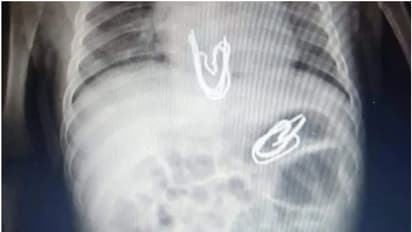

കെയ്റോ: മൂന്നു മാസം പ്രായമുള്ള കുഞ്ഞിന്റെ വയറ്റില് കണ്ടെത്തിയത് മെറ്റല് ക്ലിപ്പുകള്. ഈജിപ്തിലാണ് സംഭവം. വിശദമായ പരിശോധന നടത്തിയ ഡോക്ടര്മാരുടെ സംഘം ശസ്ത്രക്രിയയിലൂടെ അഞ്ച് മെറ്റല് ക്ലിപ്പുകളാണ് പുറത്തെടുത്തത്.

മന്സൂറയിലെ യൂണിവേഴ്സിറ്റി ചില്ഡ്രന്സ് ഹോസ്പിറ്റലിലെ മെഡിക്കല് സംഘമാണ് ശസ്ത്രക്രിയയിലൂടെ കുഞ്ഞിന്റെ ജീവന് രക്ഷിച്ചത്. കുഞ്ഞിന്റെ പ്രായത്തിനൊപ്പം മൂന്ന് സെന്റീമീറ്റര് നീളമുള്ള കൂര്ത്ത അഗ്രങ്ങളുള്ള മെറ്റല് ക്ലിപ്പുകളുടെ അപകടസാധ്യതയും ഡോക്ടര്മാര്ക്ക് വെല്ലുവിളിയായി. മെറ്റലിന്റെ കൂര്ത്ത മുനകൊണ്ട് വയറ്റിലോ ഈസോഫാഗസിലോ മുറിവുകള് ഉണ്ടായിട്ടുണ്ടോയെന്ന് അറിയാന് വിശദമായ പരിശോധനകള് നടത്തിയിരുന്നു.

എക്സ്റേയും സിറ്റി സ്കാനും നടത്തി. തുടര്ന്നാണ് കുഞ്ഞിനെ ശസ്ത്രക്രിയയ്ക്ക് വിധേയനാക്കിയത്. മൂന്നു വയസ്സുള്ള സഹോദരിയുടെ അടുത്ത് കുറച്ചു സമയത്തേക്ക് കുഞ്ഞിനെ നിര്ത്തിയ ശേഷം അമ്മ സ്ഥലത്ത് നിന്ന് മാറിയിരുന്നു. ഈ സമയം കളിക്കുന്നതിനിടെ മൂന്നു വയസ്സുകാരിയായ സഹോദരി, കുഞ്ഞിന്റെ വായില് കര്ട്ടന് ഹുക്കുകള് ഇടുകയായിരുന്നെന്നാണ് കുട്ടിയുടെ അമ്മ പറയുന്നത്. ശസ്ത്രക്രിയ വിജയകരമായി പൂര്ത്തിയാക്കി കുഞ്ഞിന്റെ ജീവന് രക്ഷിക്കാന് മെഡിക്കല് സംഘത്തിന് സാധിച്ചു.